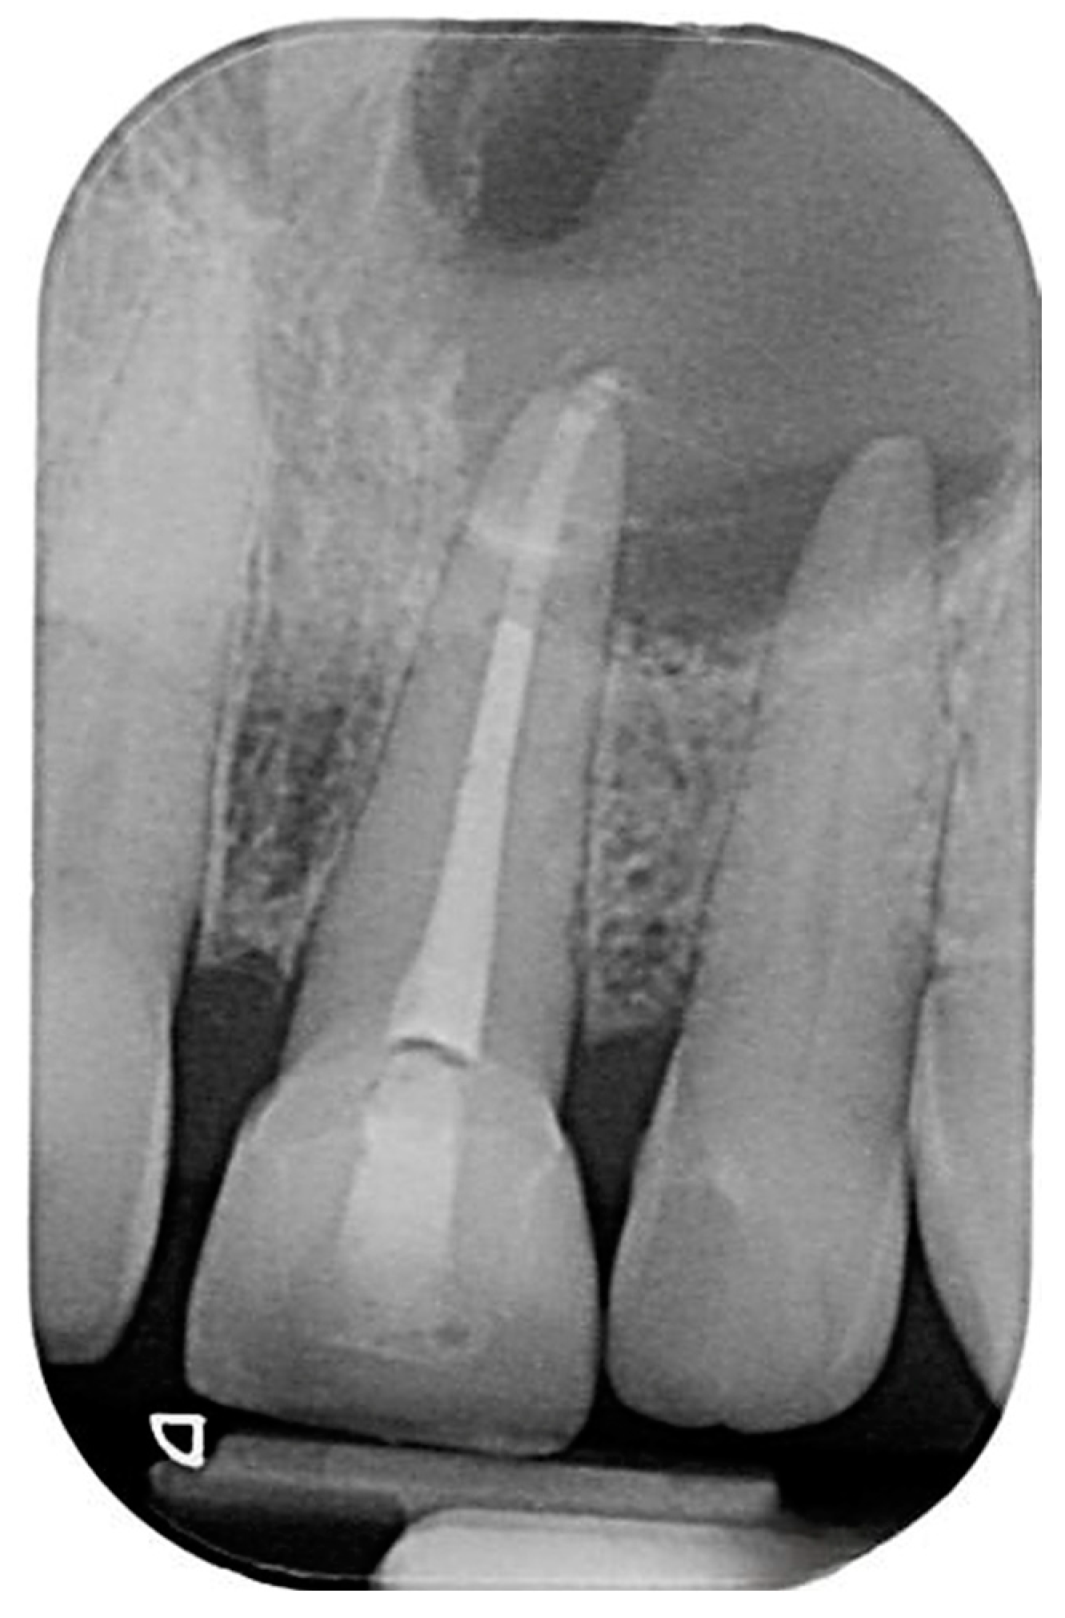

2.2. Delivery of Treatment

2.4. Healing of the Defect and Follow Up